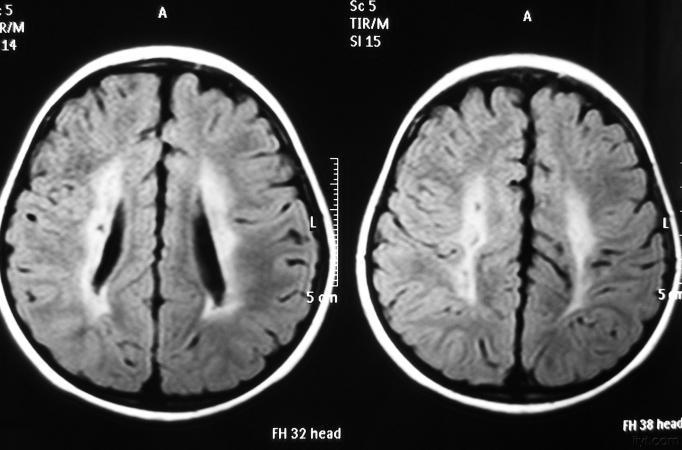

pvL

主要与脑缺血缺氧有关,多见于早产儿,是造成脑瘫的主要原因

影像学发生于侧脑室周围,侧脑室扩大,脑白质减少。扩大的侧脑室外缘常不规则为其特点,多为双侧脑室同时扩大。脑白质减少,脑皮层与脑室侧缘相近。MRI T1呈低信号,T2呈高信号。